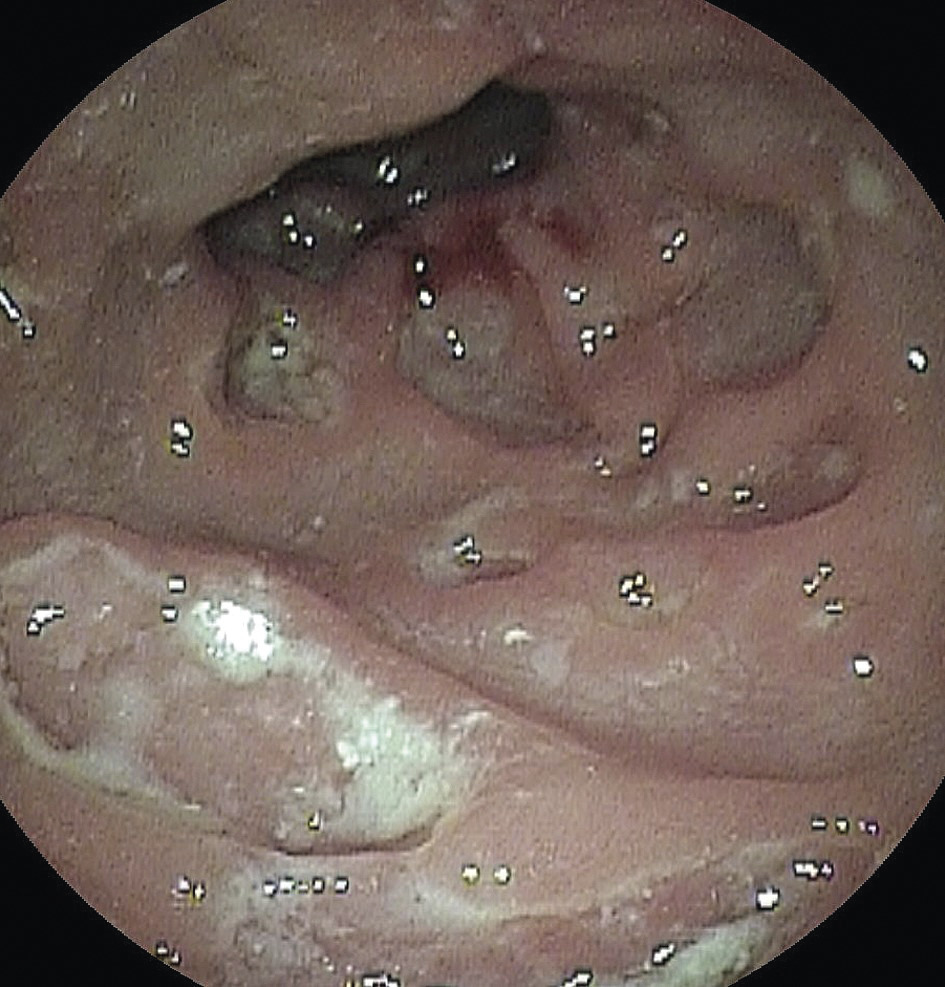

Un patient de 35 ans consulte pour des émissions glairo-hémorragiques évoluant depuis plusieurs jours. Il a des rapports sexuels avec des hommes et utilise la prophylaxie préexposition (PrEP) contre le virus de l’immunodéficience humaine (VIH). La marge anale est normale. En anuscopie, la muqueuse rectale est congestive et ulcérée (fig. 1).

La chlamydiase est une infection bactérienne sexuellement transmise fréquente. L’infection par Chlamydia trachomatis D à K donne une anorectite congestive, parfois ulcérée. L’infection par les sérovars L1, L2 et L3 est responsable de la lymphogranulomatose vénérienne (LGV), décrite en 1913 par Joseph Nicolas et Maurice Favre ; cette forme est actuellement la plus fréquente. Elle évolue en trois phases après une incubation moyenne de vingt à vingt-cinq jours : la première phase se manifeste par une ulcération anale qui passe souvent inaperçue ; une anorectite ulcérée et purulente apparaît secondairement, éventuellement associée à des adénopathies inguinales inflammatoires ; en l’absence de traitement, une sténose anorectale pseudotumorale se constitue progressivement, avec des fistules anales (fig. 2).